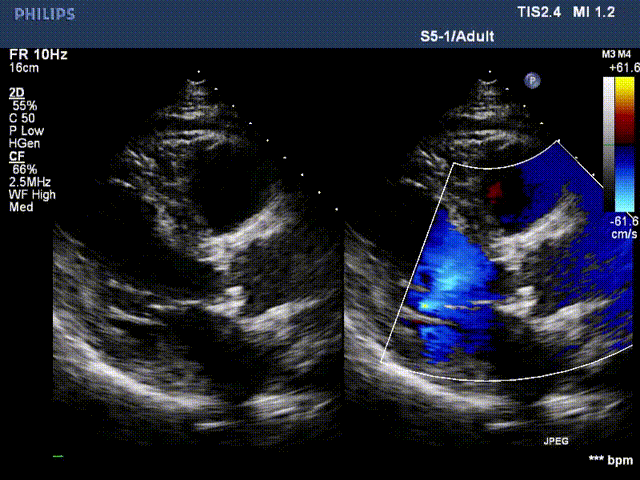

术前超声2